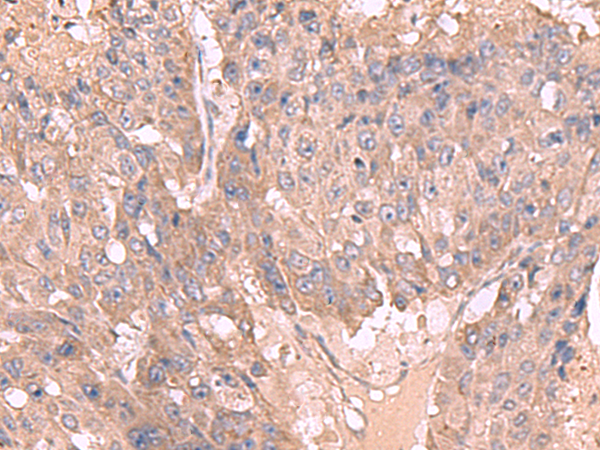

IHC positive control:

Human cervical cancer and Human colorectal cancer

IHC Recommend dilution:

50-300